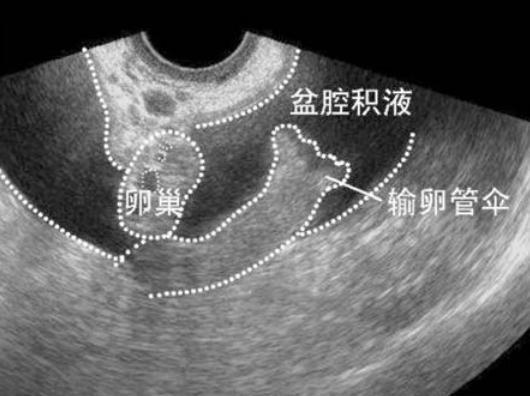

盆腔積液

盆腔積液,又分為生理性盆腔積液和病理性盆腔積液,生理性盆腔積液指的是,每當女性在排卵期,卵泡排出至盆腔中時,通過B超檢查,能夠發現盆腔中存在有少量的積液,少量的盆腔積液不屬于一種疾病,出現積液,是由于卵泡液引起的,大部分女性會因受到卵泡液的刺激,產生腹部下墜的感覺,有少部分女性在排卵期間會伴隨著少量出血的現象,這種情況不會對女性產生太大的危害無需處理。

病理性盆腔積液成語盆腔內的炎癥有很大的關系,炎癥會導致盆腔內組織出現粘連,會滲出異常的炎性分泌物,排線內會出現炎癥性積液,患者會表現出發燒腹痛的癥狀,病理性盆腔積液一定要得到專業的治療,如果沒有及時治療的話,長此以往就會引發不孕癥或女性出現慢性盆腔疼痛。

腫瘤也可能會導致女性出現盆腔積液的癥狀,如果是腫瘤引起的,往往會使盆腔內的積液量較大,通過B超檢查,能夠發現盆腔中存在大量的積液,這種情況需要進行全面的檢查,找到致病因素,采取對癥的治療,一般建議采用手術的治療方法,手術可以徹底治愈,避免再次復發,術后要保持清淡飲食。